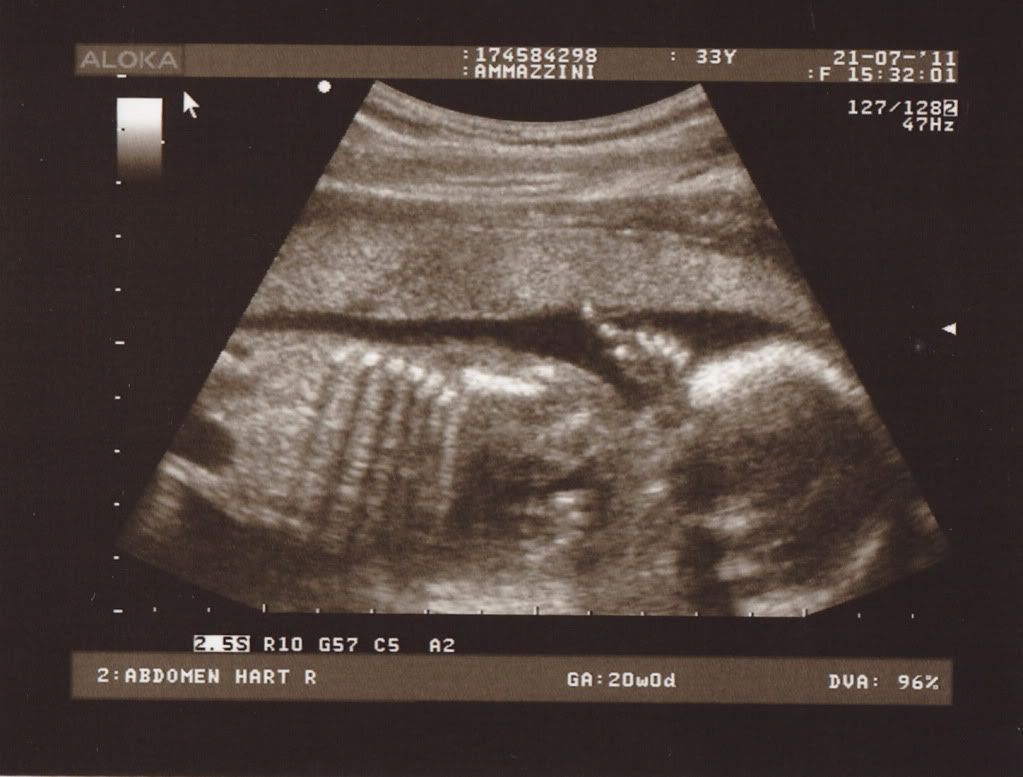

Succes met het huisje en werken, neem ook je rust he?! Wat een leuke foto, blijft indrukwekkend!!!

Ik vond al dat je nieuwe blog zo lang op zich liet wachten.. Hihi. Veel plezier en succes met t nieuwe huisje.. Enne.. Mooi echo hoor!! X

Mooie echo! Werkse deze weken! X